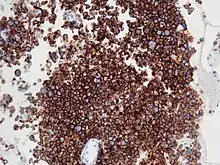

Immunohistochemistry for CD30

ALK-positive ALCL is diagnosed by histological and immunological examinations of involved tissues, typically lymph nodes. These tissues have lymphoma-like infiltrates that have variable numbers of ALCL "hallmark" cells, i.e. cells with kidney- or horseshoe-shaped nuclei that strongly express CD30 as detected by immunohistochemistry and an ALK fusion protein as detected by fluorescence in situ hybridization.[11] These cells are scattered throughout the infiltrates. WHO classifies these infiltrates into 5 patterns: a common pattern consisting of large variably shaped cells with large nuclei that typically contain multiple nucleoli (60–70% of cases); a small-cell pattern consisting of small to medium-sized neoplastic cells with clear cytoplasm and "hallmark" cells that are concentrated around small blood vessels (5–10% of cases); a lymphohistiocytic pattern consisting of small neoplastic cells along with abundant histiocytes (10% of cases); a Hodgkin's-like pattern in which the architecture resembles the nodular sclerosis pattern of Hodgkin lymphoma (3% of cases); and a composite pattern consisting of two or more of the just described patterns (15% of cases).[9] Detection of circulating autoantibody against ALK supports the diagnosis.[10] Individuals with low levels of these autoantibodies are at an increase risk of relapsing after treatment.[9]